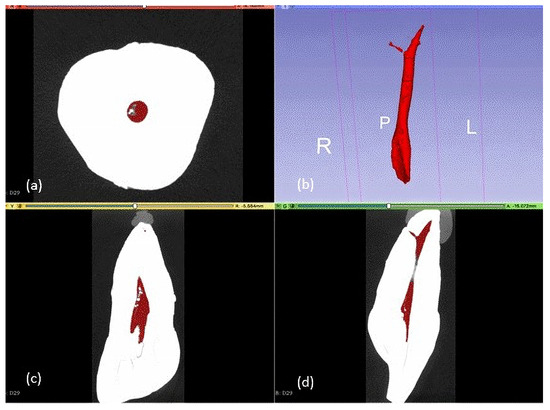

2.2. CBCT Study

2.3. Micro-CT Study